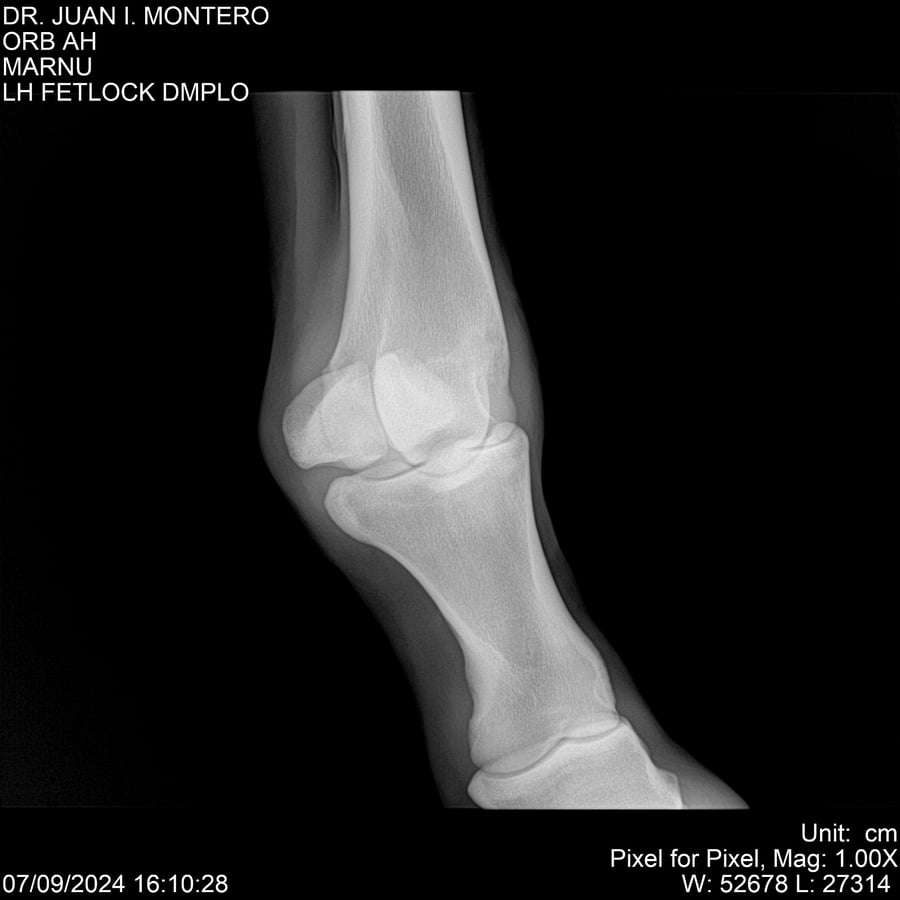

LOTE 21, ORB AH Lote Anterior Volver al remate Lote Siguiente Ficha Contacto Montevideo - Ficha del Lote Identificador: #282519 Categoría: Yeguarizos Montevideo - 57 Visualizaciones ClicData Contacto Empresa: Abelenda N. R., Walter Hugo Nombre*: Teléfono* : E-mail* : Mensaje Enviar Registrese gratis Este contenido Exclusivo está disponible sólo para usuarios registrados Ingresar